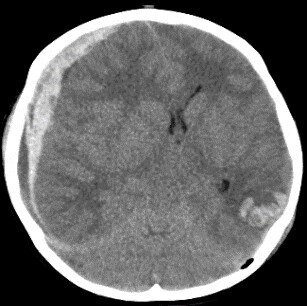

3.頭部外傷

当院は3次救急に対応しており、神奈川県ドクターヘリの基地病院です。そのため、多くの頭部外傷の患者さんを受け入れています。救命救急科と連携して速やかな治療を提供しており、特に頭部単独外傷の場合には手術室搬入までの時間を30分以内とするよう心がけて日々努力しています。(画像は急性硬膜下血腫・脳挫傷・気脳症の患者の頭部CT)